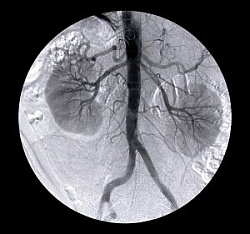

Cievna sieť obličiek je mimoriadne hustá, aby mohli spoľahlivo kontrolovať a udržiavať hladiny dôležitých látok v krvi a zároveň ju zbavovali toxínov. Chronické ochorenie obličiek (CKD) postihuje celosvetovo až 500 miliónov ľudí, čo predstavuje asi každého desiateho obyvateľa. Pri tomto ochorení postupne klesá funkcia obličiek a ak sa zníži asi na desatinu pôvodného „výkonu“, hovoríme o zlyhaní obličiek.